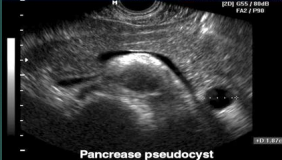

Pseudocyst

Most common cystic lesion of the pancreas

Fluid-filled loculus with no epithelial lining

Located outside the pancreas often in lesser sac

Pancreatic tissue is damaged and leaks enzymes and body fluid to form a cyst

Often occurs in the tail